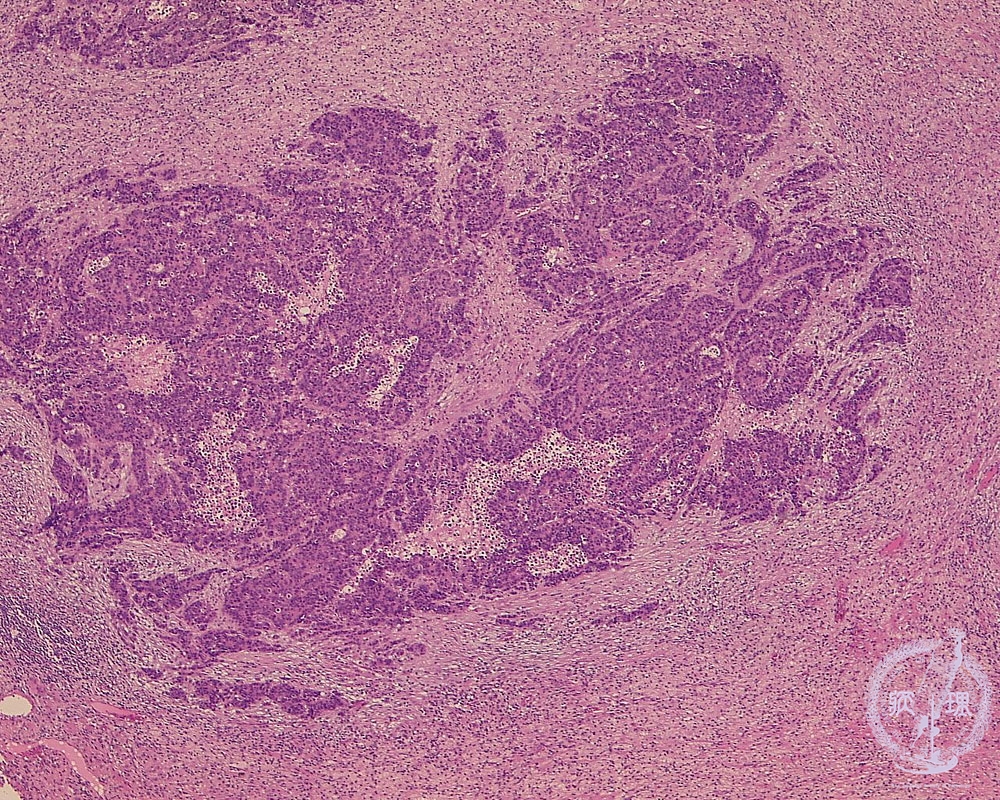

Microscopic view (HE stain, low power view): Small cell carcinoma of lung. The neoplastic cells are small with a high N/C ratio and they proliferate diffusely with no characteristic pattern.

Click the image to see the enlarged image.